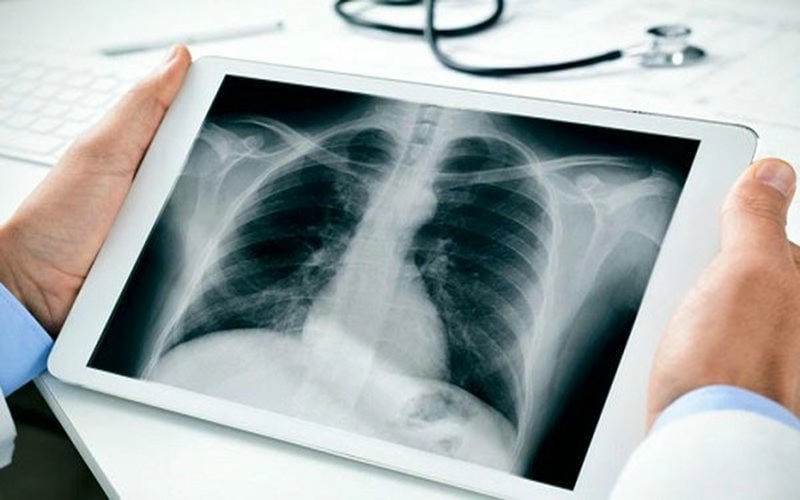

Hình ảnh bệnh lao phổi là tài liệu tham khảo quan trọng giúp người bệnh và bác sĩ dễ dàng nhận biết dấu hiệu bất thường. Việc quan sát hình ảnh X-quang, CT phổi giúp chẩn đoán chính xác mức độ tổn thương và đưa ra phương án điều trị kịp thời.

Bạn sẽ phải rùng mình khi chiêm ngưỡng hình ảnh bệnh lao phổi là như thế nào dưới ống kính y học thực tế. Những bức ảnh chụp X-quang cho thấy phổi bị tổn thương nặng, xuất hiện những đốm trắng mờ như bóng ma ám ảnh. Không chỉ là các tổn thương vật lý, đây còn là những “chứng tích sống” của căn bệnh âm thầm hủy hoại cơ thể qua từng hơi thở. Từ viêm nhẹ đến tổn thương lan rộng, hình ảnh bệnh lao phổi khiến người xem không thể rời mắt vì mức độ nghiêm trọng mà nó thể hiện rõ ràng qua từng chi tiết.